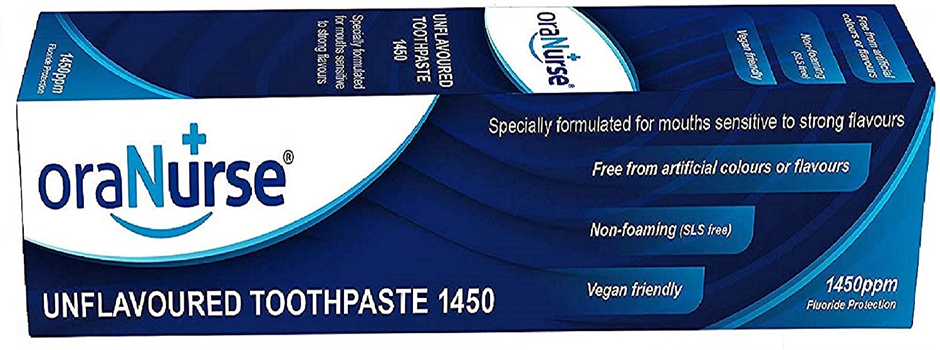

My child does not like the taste or the feeling of toothpaste in their mouth. What can I do?

You can buy unflavoured and non-foaming fluoride toothpaste which they may prefer to regular toothpaste.

Disclaimer: we do not endorse any particular brand of product; these are all examples of what has been described.